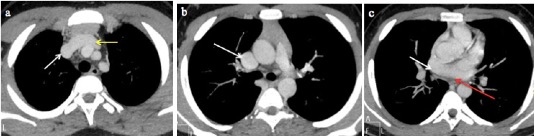

Fig. 3 A 2-month-old male infant with tetralogy of Fallot and a retroaortic left innominate vein. (a, b) CTPA axial MIP images show the retroaortic left innominate vein (white arrow). c) Axial MIP image shows a ventricular septal defect (yellow arrow). d) Sagittal MIP image shows overriding of the aorta (red arrow). e) Axial MIP image shows a right-sided aortic arch (white arrow). f) Axial MIP image shows narrowing of the main pulmonary artery (green arrow), and its right and left branches.

AA: Ascending aorta, RA: Right atrium, LA: Left atrium, RV: Right ventricle, LV: Left ventricle

Various innominate vein anomalies were identified in this study, including retroaortic left innominate vein (Figure 3), retroesophageal left innominate vein, double left innominate vein and left innominate vein coursing behind the right innominate artery. These aberrant courses are commonly associated with CHD involving right outflow obstruction, such as TOF4,16-17. Other cardiac malformations linked to these anomalies include pulmonary atresia, VSD with patent ductus arteriosus (PDA), VSD with TAPVC, right aortic arch, and PDA4,16,17,23. In this study, similar associations were noted such as pulmonary atresia, TOF, right-sided aortic arch, septal defects and one case of truncus arteriosus. While echocardiography and catheter angiography can identify these left innominate vein anomalies, MDCT offers superior cross-sectional visualization, allowing for comprehensive anatomical delineation5-17.